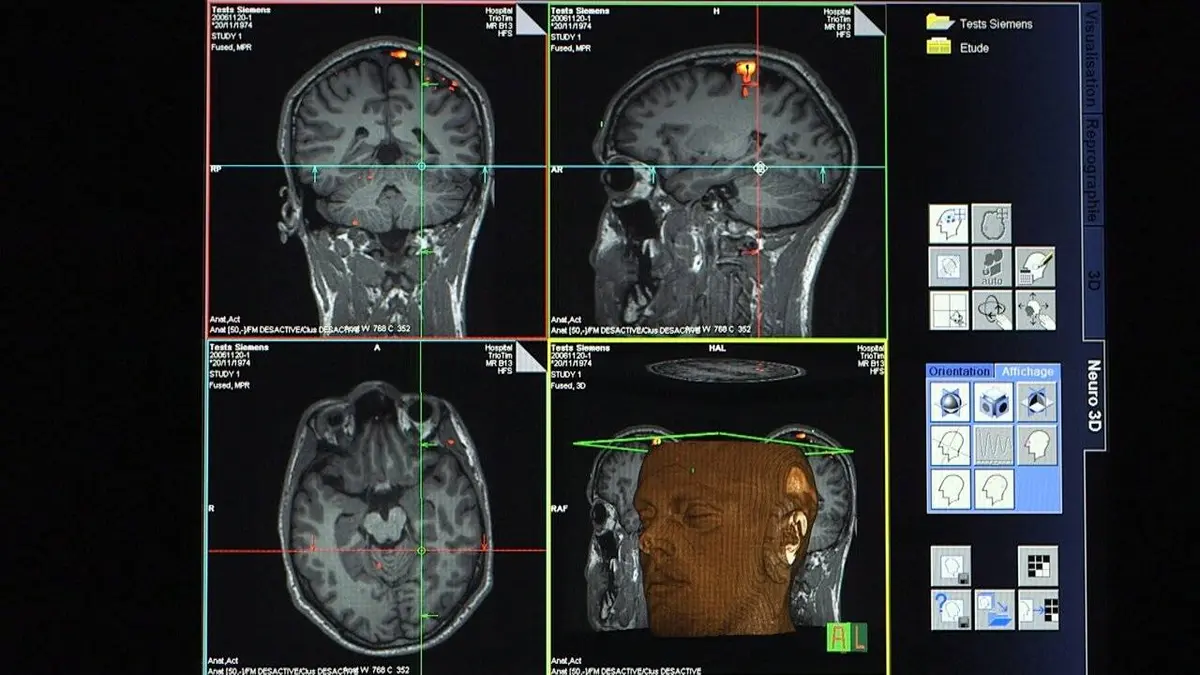

Je supprime la publicitéEnquête au coeur du Neurospin, le plus grand complexe mondial dédié à l'exploration du cerveau, une plateforme ultra-moderne qui repousse sans cesse les limites de l'imagerie cérébrale.

Vidéo Voir le cerveau penser